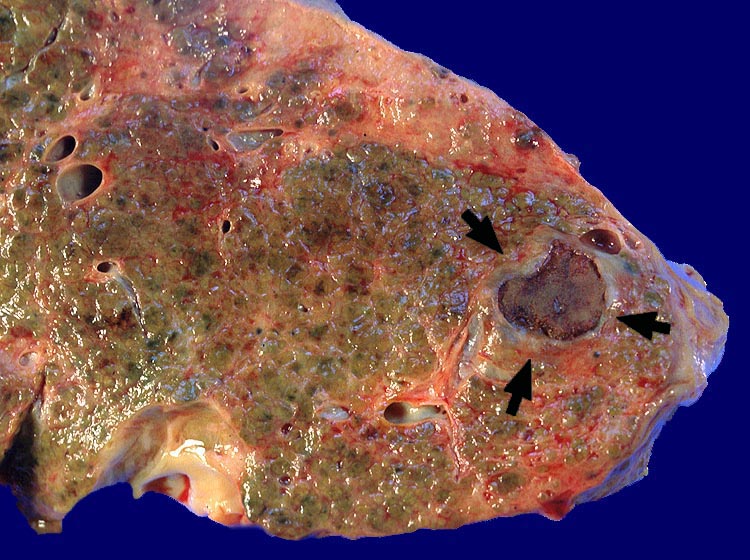

Fibrös abgekapseltes vollständig nekrotisches hepatozelluläres ► Karzinom. Feinknotiger zirrhotischer Umbau.

Zirrhose bei chronischer Hepatitis C und Alkoholabusus. St.n. Alkoholinjektion in einen solitären Herd eines hepatozellulären Karzinoms vor 3 Jahren.